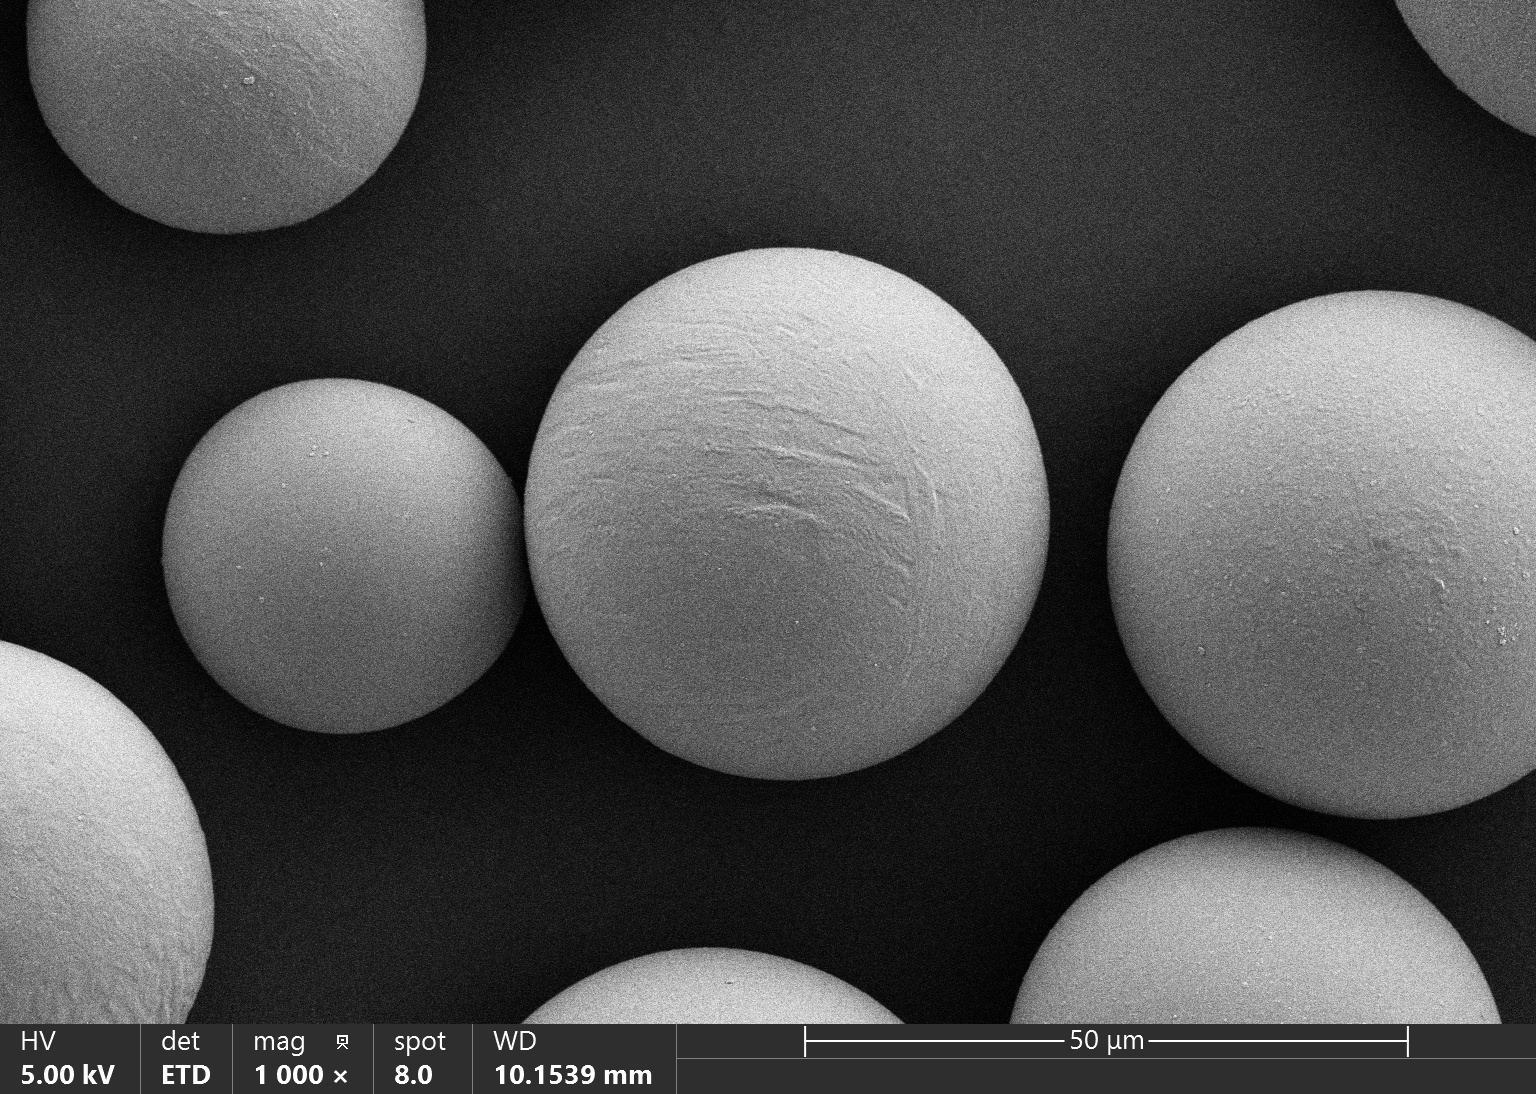

Vita Spire has developed HAp microsphere products for next-generation aesthetic fillers. We offer three different products, each varying in porosity, which corresponds to different degradation rates after injection. Our HAp microspheres provide versatile options for creating specialized, high-quality aesthetic treatments.

| HAPAI-01 | Hydroxyapatite (HAp) Microspheres for Aesthetic Injection, Type I | N/A | Details |

| HAPAI-02 | Hydroxyapatite (HAp) Microspheres for Aesthetic Injection, Type II | N/A | Details |

| HAPAI-03 | Hydroxyapatite (HAp) Microspheres for Aesthetic Injection, Type III | N/A | Details |